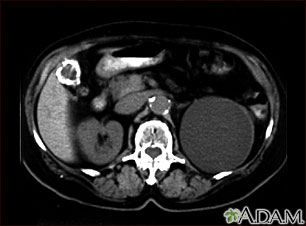

- Abdominal CT scan